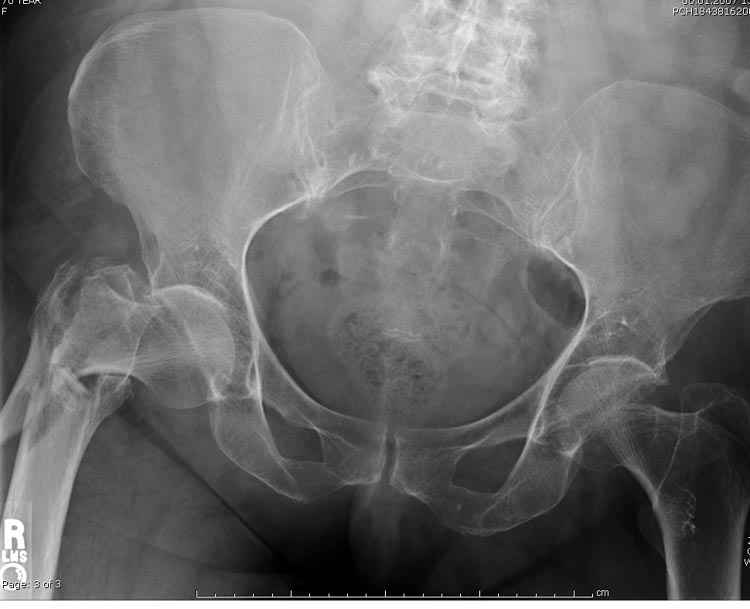

А что тут заставляет сомневаться? Здесь настолько очевидно предпочтителен закрытый интрамедуллярный остеосинтез реконструкционным стержнем (проксимальные гвозди толстоваты для такого молодого возраста), что закрадывается мысь о каком-то подвохе.

Не солидно экономить на пленке, это не делает чести презентации. Такие ограниченные нестандартные снимки приводят к тактическим ошибкам.

Предугадать распространение линий перелома при чрезвертельных и оскольчатых переломах трудно, поэтому для принятия правильного решения рекомендуется Компьютерно Томографические исследование.

При отсутствии КТ, снимок на вытяжении поможет увидеть общую картину расположения отломков, особенно потенциальные места введения импланта. Риск раскола в этом случае огромный, поэтому больной должен быть дообследован.

А так для лечения оскольчатых переломов подходят все методы, включая интра- и экстрамедуллярные в зависимости от опыта и наличия импланта.

Здесь пара похожих случаев.

Увожаемый коллега,мое мнение:фиксация и\медул.блок. стержнем Gamma-long "STRYKER". Вероятно, закрыто сделать полностью может не получится. Откроетесь на 6-8 см. для репозиции промежуточного фрагмента, но только после установки стержня. Удачи!!!